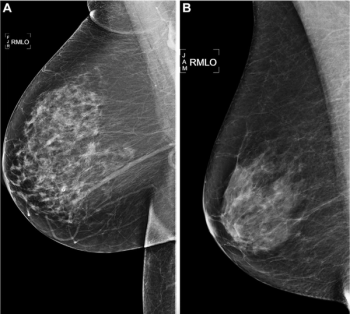

In a large retrospective study involving over 523,000 digital breast tomosynthesis (DBT) exams and over one million digital mammography (DM) exams, researchers found that DBT was associated with significantly lower recall rates but showed no advantage over DM in the diagnosis of interval or advanced breast cancer.

Six reader studies on digital mammography revealed a pooled sensitivity rate of 80.8 percent for stand-alone artificial intelligence (AI) in comparison to 72.4 percent for radiologist assessment while seven historic cohort studies showed a 75.8 percent pooled sensitivity rate for stand-alone AI versus 72.6 percent for radiologist interpretation of digital mammography.

In multiple mammography datasets with the original radiologist-detected abnormality removed, deep learning detection of breast cancer had an average area under the curve (AUC) of 87 percent and an accuracy rate of 83 percent, according to research presented at the recent Society for Imaging Informatics in Medicine (SIIM) conference.

Five artificial intelligence (AI) algorithms for mammography assessment were better at predicting breast cancer risk over five years than the Breast Cancer Surveillance Consortium (BCSC) risk model, according to new retrospective research involving over 13,000 women.